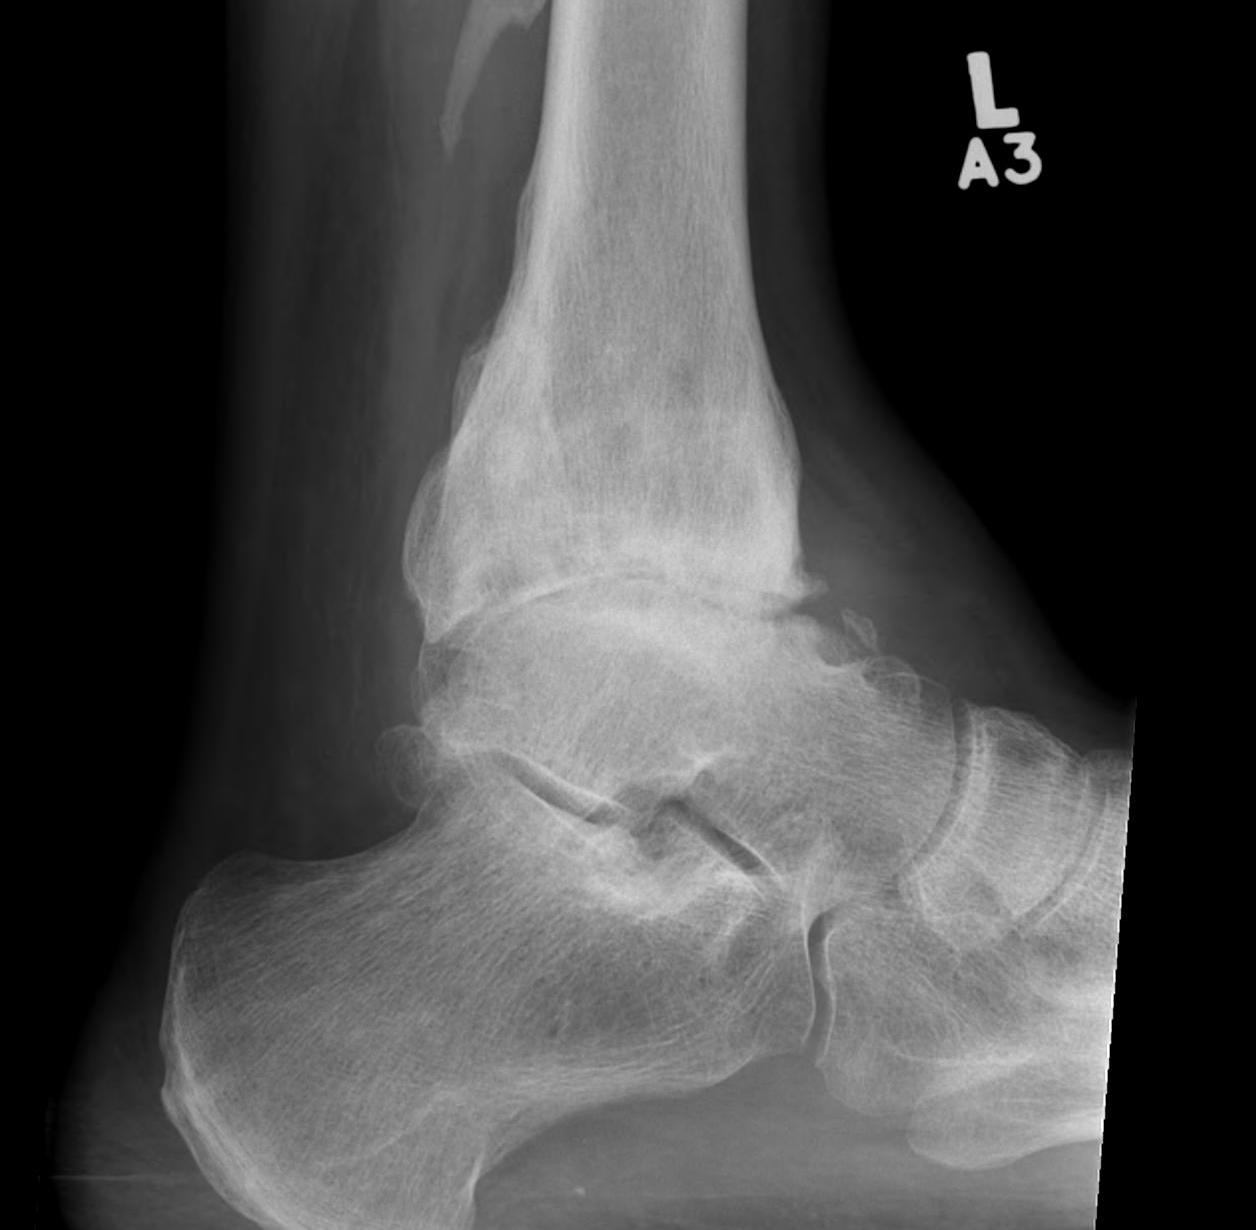

• Ankle Arthrodesis